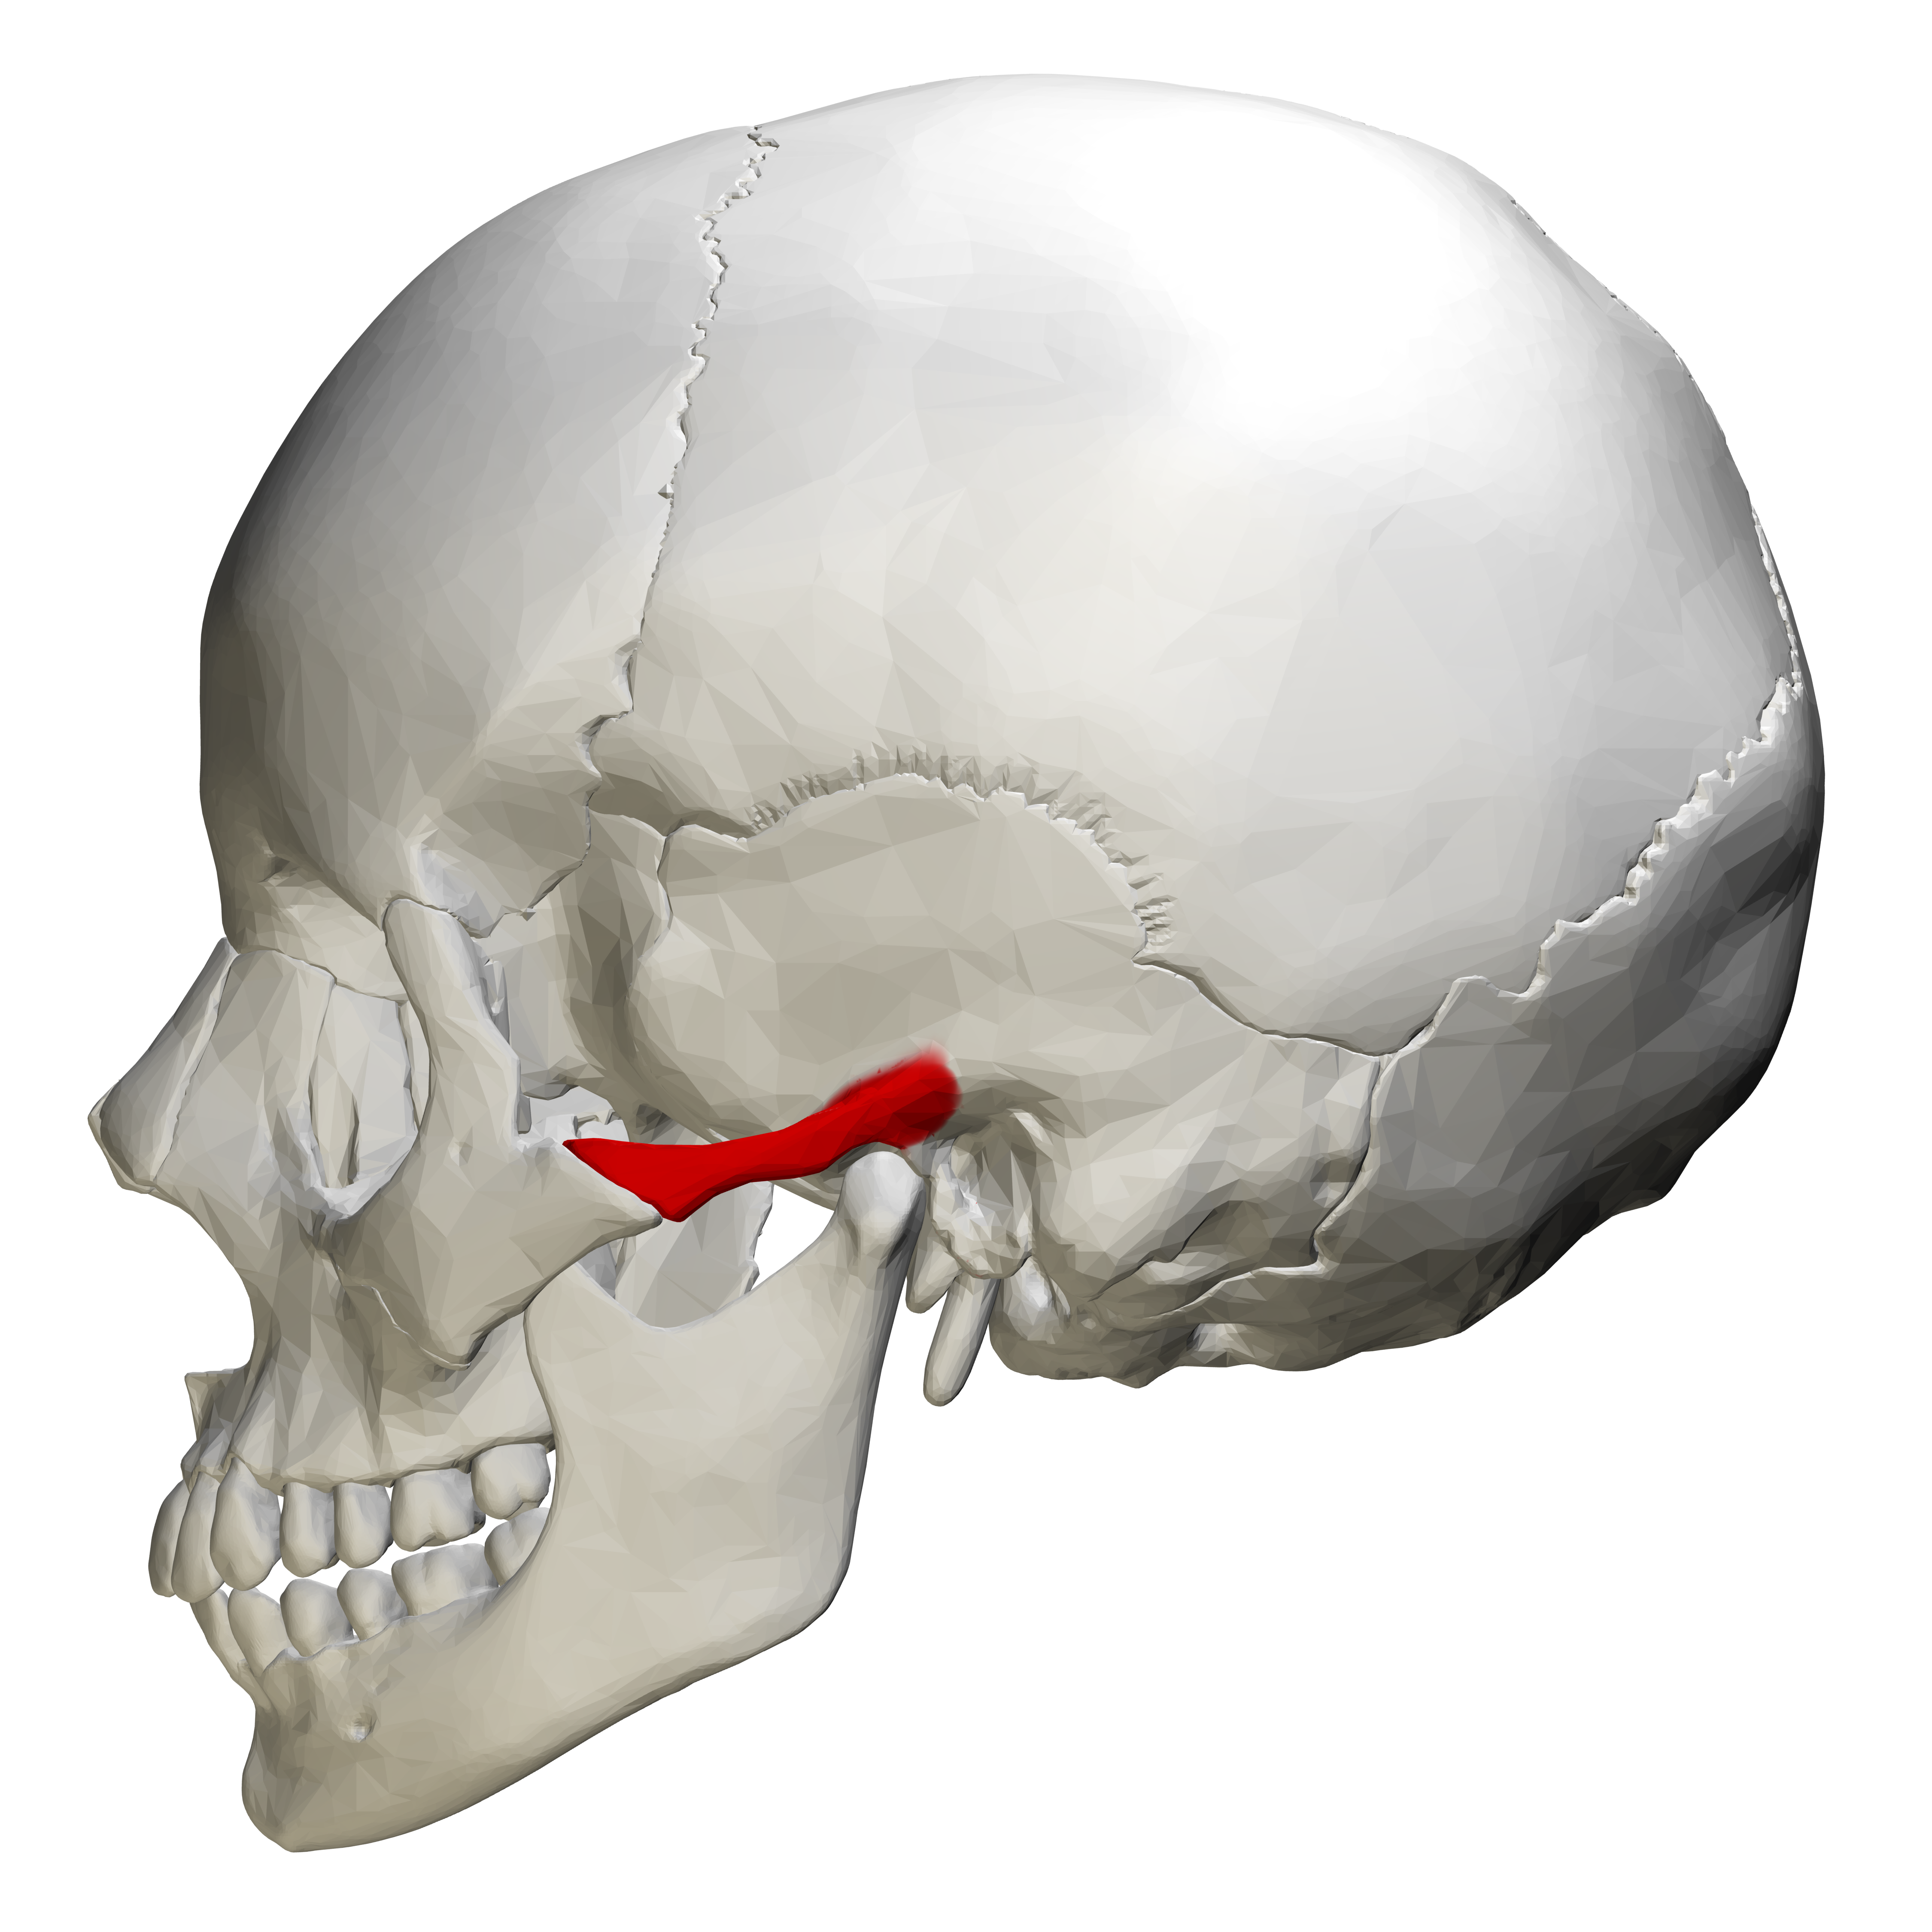

КТ анатомия сосцевидного отростка: особенности и показания